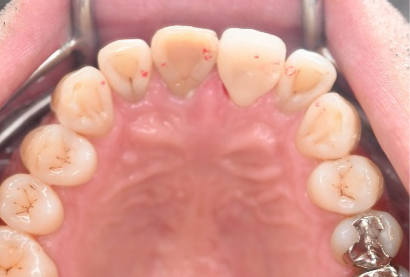

虫歯の治療をするときに、銀歯や白いかぶせ物をすることがありますが、細菌がつきやすい素材とつきにくい素材があることをご存知ですか?患者さんのお口の中を見ますと、銀歯や保険のプラスチック製の白いかぶせ物にはプラーク(歯垢:細菌のかたまり)がたくさんついていますが、陶器製の『オールセラミック』の被せものには、プラークがほとんどついていません。

銀歯やプラスチックは、お口の中で酸化、劣化したり細かい傷がついたりして、表面にプラークがつきやすくなります。プラークの中に棲みついている虫歯菌は虫歯の再発(2次カリエス)を引き起こし、歯周病菌は歯ぐきに炎症を起こして歯周病を引き起こします。

一方、オールセラミックはほとんど劣化しませんし、表面に傷もつきにくいので、プラークがつきにくい状態が保てます。虫歯の再発や歯周病になるリスクも、その分減ります。

オールセラミックは他にも、白くて見た目がきれい、金属アレルギーにならない、歯ぐきに黒いしみ(メタルタトゥー)ができない、口臭がしにくいというメリットもあります。歯を良い状態で長持ちさせるためには、オールセラミックは他の材料よりも優れていると思います。